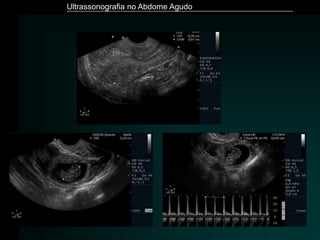

Pancreatite Aguda - Complicações

• Flegmão (18 – 30%)

• Pseudocisto (10%)

• Necrose (infectada ou não) (10%)

• Abscesso (3%)

• Complicações vasculares (trombose, pseudoaneurisma)

• Ruptura

• Hemorragias

H’Icm, Gastroenterol Clin N Am 19(4) 811-842,1990

Ultrassonografia no Abdome Agudo

Hayes. Eur Radiol (2004) 14:L123–L137